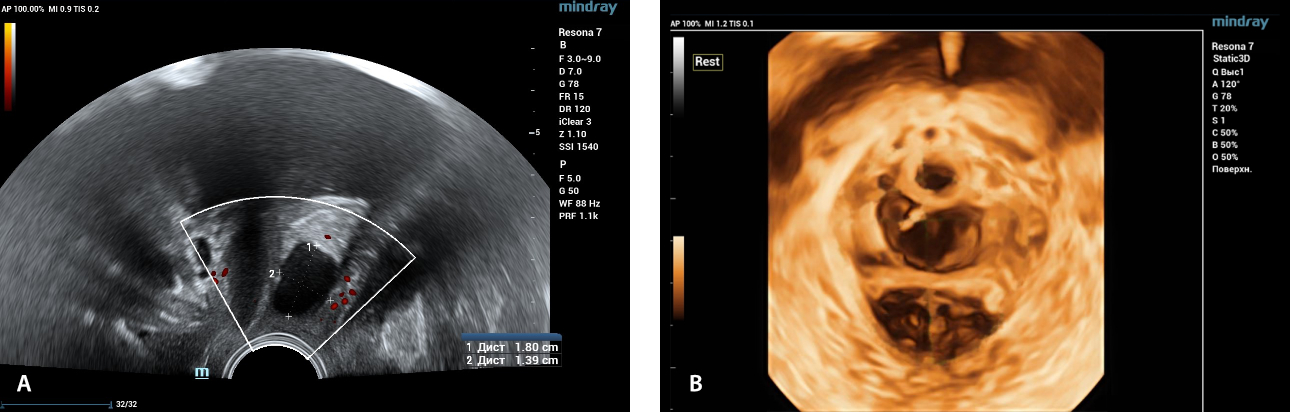

?? ?? ??? ?????(Endocavity volume convex array transducer)(DE10-3WU, Resona 7, ?????)? ??? ??? ???, ??? ?? 1/3 ?? ? ??(anterior vaginal wall)? ???? 18x14 mm ??? ?? ??(an ovoid-shaped formation) with a parietal fine suspension, ????? ??? ???? ??(non-displaced), ????,? CDI ??? ?? ?? ???? ????????. 3D ??? -? ??? ? ??(hyperechoic septa)? ?? ???? ??? ?? ??.

?? ??? ?? ???(Volumetric reconstruction)? ??? ??? ?? ??? ?? ??? ??? ? ??? ?? ??????? ??? ??? ??? ???.